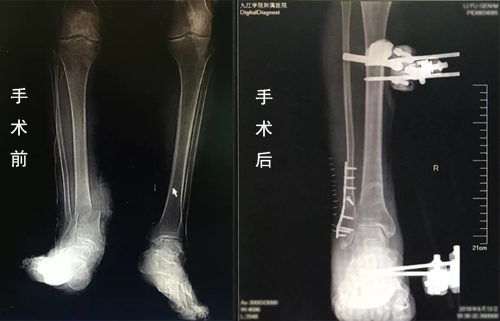

临床医学院/附属医院显微外科医护团队与麻醉科、手术室、输血科等进行了充分的术前讨论,制定好周密的麻醉及手术方案。由许刚主治医师主刀,赵斌副主任医师,赵庆飞、刘秭洋医师共同为患者实施了右小腿离断伤再植术。经过4个多小时的艰苦奋战,手术顺利完成小腿骨折、血管、神经、肌腱及皮肤的修复。术后由科室护理团队制定了详细的护理计划,严密观察患者生命体征及切口情况,全程进行细致护理。通过科室全体医护人员的共同努力,李大爷术后恢复各项指标良好。

据李军副主任介绍,断肢再植是一个体现医院显微外科能力的标志性手术。此患者受伤后断肢从表面上看有少量皮肤和肌肉组织将断肢与机体相联,但实际上这部分离断肢体已无血液供应和神经支配,已成为毫无活力的组织,这为再植手术的成功增加了难度;另外,老年患者的血管条件不好,是再植的又一个难点。此次手术用到了血管搭桥技术和神经束的吻合,手术难度系都数非常高,尤其是患者处于失血性休克状态,对医师的要求就更高。